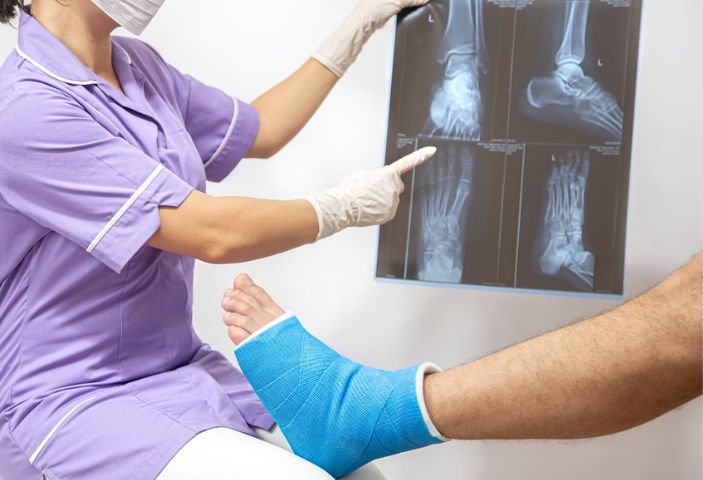

석고 붕대 고정은 골절 치료의 일반적인 방법입니다. 석고 또는 유리섬유로 만들어진 붕대를 골절 부위 주변에 단단하게 감아 깁스합니다. 이 방법은 골절 부위를 수주간 움직이지 않도록 고정하여 자연적인 회복을 돕습니다.

홍옥 종합병원에서는 초경량 유리섬유 붕대를 광범위하게 사용합니다. 이 붕대는 기존 석고 붕대의 1/8에 불과한 무게로, 20배 더 빠르게 굳어 환자의 통증을 신속하게 줄이고 치료 시간을 크게 단축시킵니다. 또한 유리섬유 붕대는 방수 기능이 있어 환자가 샤워 등 일상생활을 할 때 붕대가 젖을 염려가 없습니다.